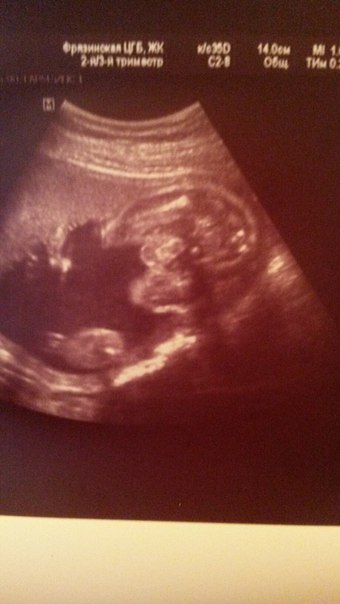

Узи 23 недели.

Сходила сегодня на узи посмотреть малышечку, а там сюрприз. Крупный мальчуган с внушительным достоинством, так что все мысли о девочке, остались в кабинете узи. С малышом все хорошо, угрозу сняли и тонус тоже. Единственное, что меня напугало, так сказали что голова у нас большая, не по срокам. Узистка говорит, что скорей всего просто из-за сроков, они больше, Пока не паниковать, ждать следующего узи.

Бипариентальный размер головы - 59 -24 нед.

Длина бедренной кости левой: 43-24 нед.

Диаметр/окружность живота : 56 - 23-24 нед.

ОЖ- 190 -23-24 нед.

ЧСС-144

Плацента расположена по передней стенке матки. Толщина плаценты до 24 мм.

Степень зрелости -1

Пуповина имеет 3 соседа

Внутренний зев сомкнут 45 мм

Заключение: Беременность 23-24 нед. Поперечное положение плода.